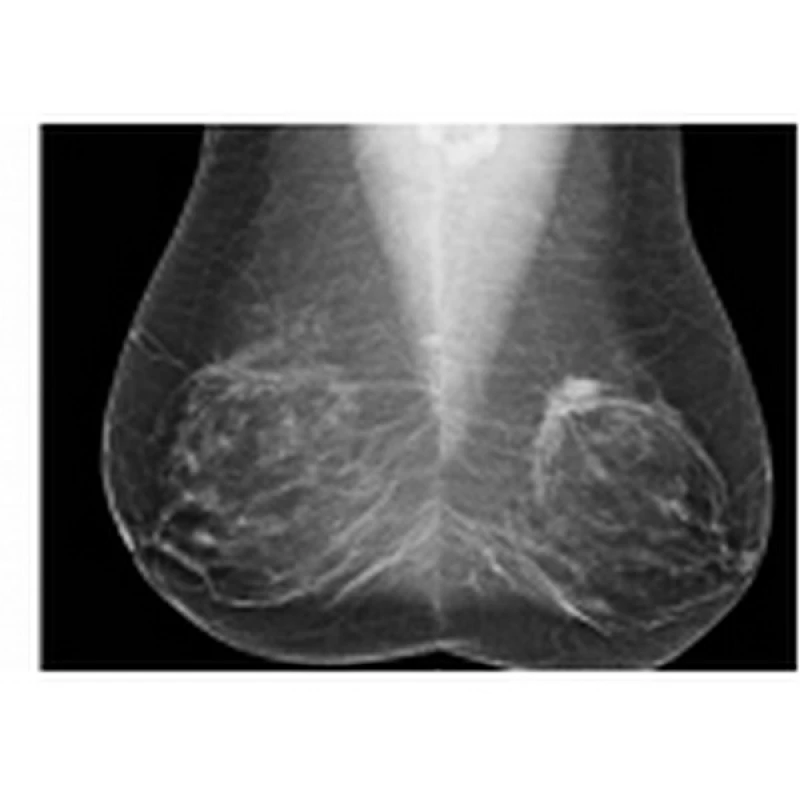

Você está precisando de um mastologista para homens preço Vila Madalena? A Clínica Bem Estar pode ajudá-lo. Apesar de raras, algumas doenças mamárias podem estar presentes nos homens. Como exemplo, a ginecomastia, que é responsável por 85% das massas palpáveis na mama masculina. Temos, ainda, o câncer de mama que incide em 0,8-1% dos homens e, normalmente, está associado a alguns fatores de risco.